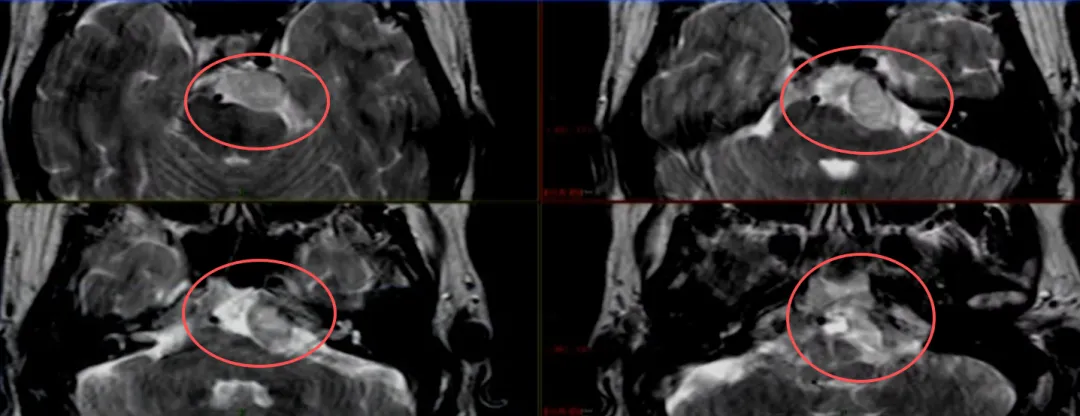

岩斜区位于颞骨岩部背面与枕骨斜坡部的岩斜裂汇合处,从岩骨尖至颈静脉孔。内侧至斜坡中线,外侧至第Ⅴ、Ⅶ和Ⅷ脑神经,上缘为鞍背,下缘为颈静脉孔水平;下方为枕骨大孔区。岩斜区肿...